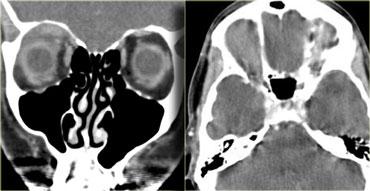

Bệnh mắt tuyến giáp

Hãy quan sát các hình ảnh bên trái, mô tả chúng và đưa ra chẩn đoán phân biệt, đồng thời tạm thời bỏ qua tiêu đề của đoạn này.

Chẩn đoán là bệnh mắt tuyến giáp và chẩn đoán phân biệt là giả u hốc mắt.

Chúng ta sẽ thảo luận ngay sau đây về cách phân biệt hai bệnh lý này.

Trước đây, thuật ngữ bệnh nhãn khoa Graves được sử dụng.

Tuy nhiên, điều này gợi ý rằng bệnh nhân đang trong tình trạng cường giáp.

Ngày nay, chúng ta biết rằng những bệnh nhân được điều trị bệnh Graves có thể có chức năng tuyến giáp bình thường hoặc thậm chí suy giáp mà vẫn có thể phát triển bệnh mắt tuyến giáp, do đó hiện nay chúng ta sử dụng thuật ngữ bệnh mắt tuyến giáp.

Nguy cơ lớn nhất của bệnh mắt tuyến giáp là bệnh lý thần kinh thị giác do chèn ép, có thể do chèn ép trực tiếp bởi các cơ hoặc do thiếu máu cục bộ gây ra bởi sự chèn ép các mạch máu.

Đặc điểm then chốt cần tìm kiếm là đỉnh hốc mắt.

Nếu không thấy mô mỡ xung quanh đỉnh hốc mắt, khả năng cao có tình trạng chèn ép.

Những bệnh nhân này được điều trị bằng phẫu thuật giải áp qua nội soi, trong đó thành trong của hốc mắt (tức là lá giấy – lamina papyracea) được phá vỡ.Giả u

Bệnh có thể ảnh hưởng đến mọi thành phần của hốc mắt: cơ, gân, mô mỡ, thần kinh thị giác, bao thần kinh, tuyến lệ, v.v.Điểm phân biệt then chốt giữa giả u và bệnh mắt tuyến giáp là trong giả u, không chỉ các cơ mà cả các gân cũng bị tổn thương.

Trên hình ảnh bên trái ngoài cùng, hãy chú ý sự thon nhỏ dần của cơ bị phù nề tại điểm bám gân ở bệnh nhân mắc bệnh mắt tuyến giáp.

Bên cạnh đó là hình ảnh của bệnh nhân mắc giả u.

Hãy chú ý rằng tình trạng phù nề lan rộng đến tận điểm bám gân.Bệnh lý ngoài nón cơ